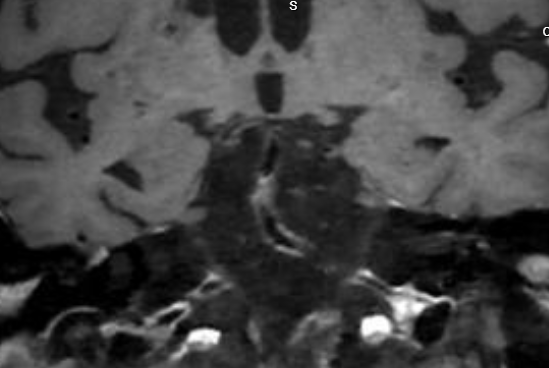

今年12月,王爷爷又因反复头晕回来复查。血管造影提示,基底动脉中段出现了重度狭窄(如图1),血管斑块处于不稳定状态(如图2),就像一颗“定时炸弹”,随时可能再次引发卒中,具备强烈的手术指征。

图2:基底动脉次全闭塞,管壁增强可见斑块不稳定状态。